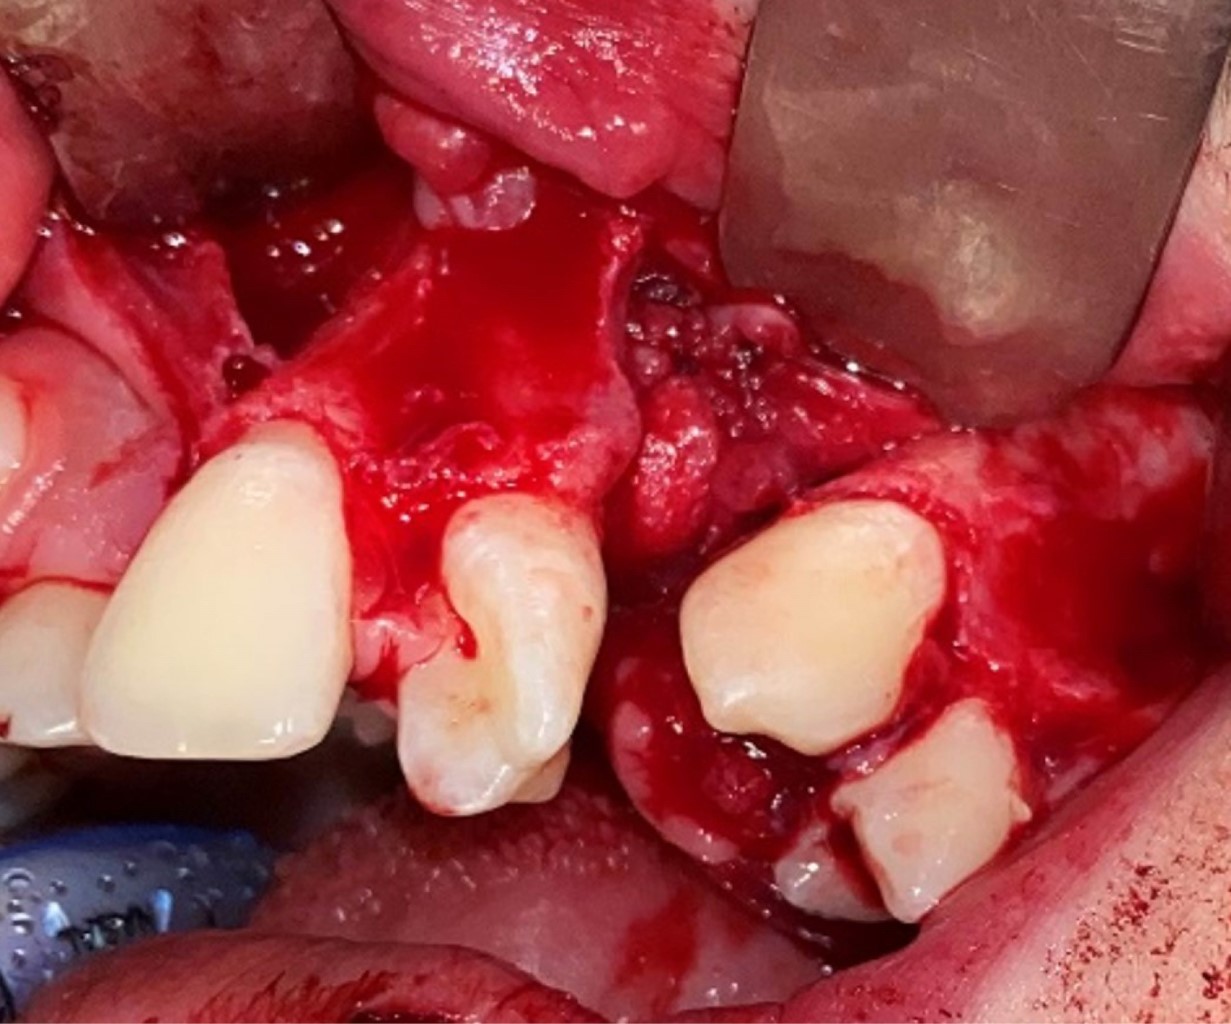

Figure 1

Figure 2

Figure 3

Figure 4

Figure 5

Figure 6

Figure 7